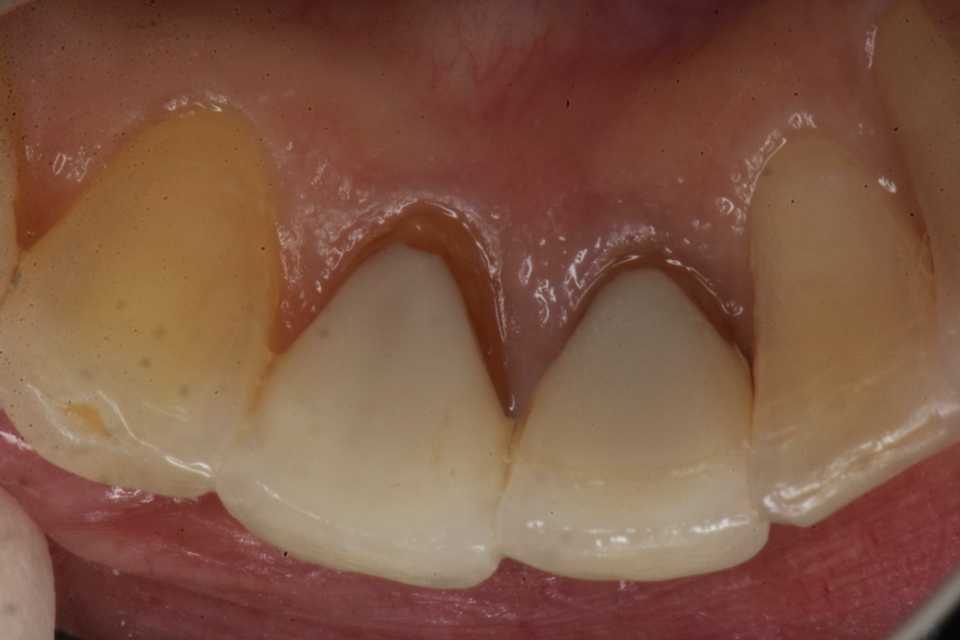

治療5ヶ月後 、病巣は小さくなってきている。GAも消えている。

既存の根管充填材を全部除去する必要はない。そこまで届けば良いだけだ。

なぜなら根管充填材と根管壁の間には思われている程の緊密性はなく隙間があり、そこから細菌が侵入して根尖に病巣ができるのだから、逆にその隙間から抗菌剤を届かせることができるわけだ。

3MIX+α-TCP​を根管充填材の上縁まで届かせることができればよい。